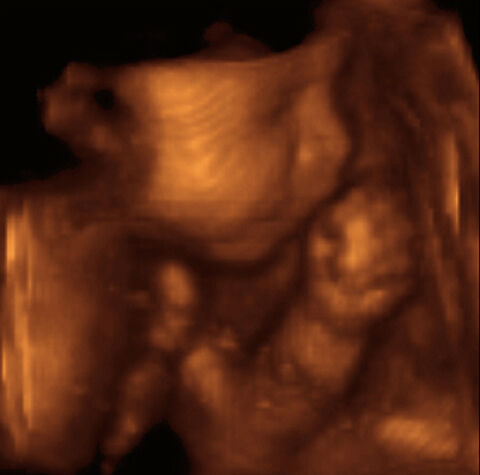

Newer ultrasound technology allows medical professionals to get a very detailed ultrasound image. High resolution ultrasounds as well as the new "3D" and "4D" ultrasounds can give you a really clear picture of your baby, almost like having a photograph of your new arrival before baby arrives! 3D ultrasounds generate a 3D still image of your baby while 4D ultrasounds create a 3D moving image of your baby.